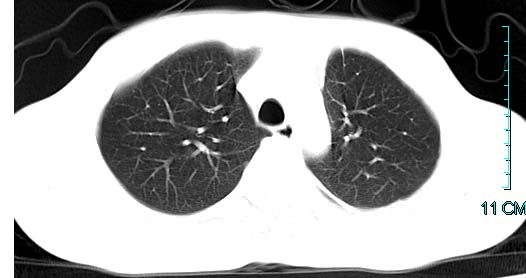

以下是引用ctkz987在2006-3-28 13:04:00的发言:[br]左侧胸腔积液穿刺后多发气液平(多房性),结合临床有高热不除外合并感染。

以下是引用qian在2006-3-28 14:32:00的发言:[br]左肺下叶大片状阴影,密度不均,见有条片影和空洞及气液平,少量胸腔积液伴有胸膜增厚,从图像看积液密度比水的密度高,结合病史,考虑左下肺化脓性炎症伴有脓胸。

以下是引用wawaquan在2006-3-28 22:25:00的发言:[br]左上肺舌段多发斑片影。结合“男24y咳嗽咳痰气促伴高热(38.5--39.5)20多天”及穿刺史,[br]考虑1 左下肺化脓性炎症;2脓胸。

以下是引用乡医在2006-3-28 18:37:00的发言:[br]左侧多发液气平面结合患者男24y咳嗽咳痰气促伴高热(38.5--39.5)20多天,查胸水:ldh239.3,总蛋白59.19,tb-ab阴性,利凡它试验+,红c2.7*109,白c1.08*109,分类淋巴92%分叶8%,考虑1脓胸2肺隔离征感染